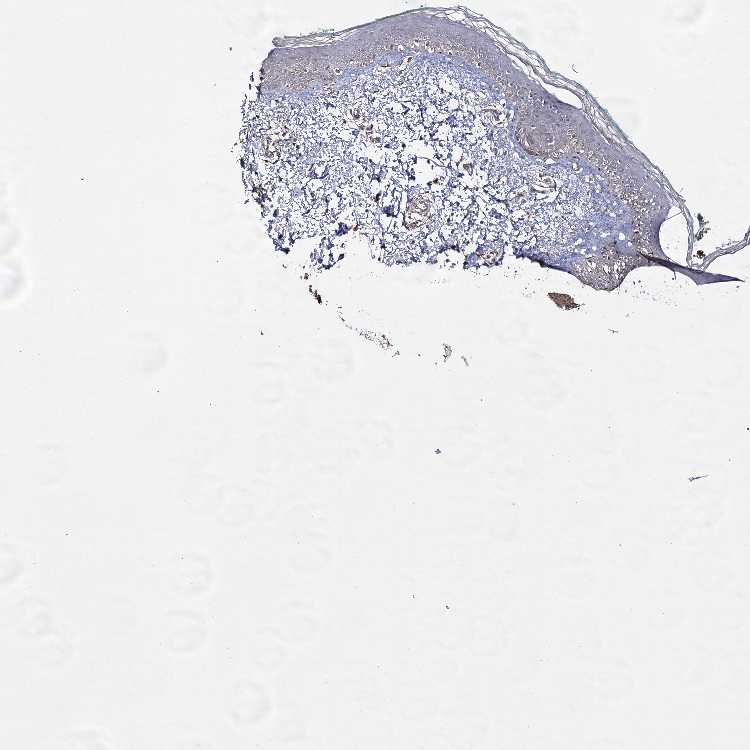

SKIN 1 - Antibody stainingi

Antibody staining in the annotated cell types in the current human tissue is reported as not detected, low, medium, or high, based on conventional immunohistochemistry profiling in selected tissues. This score is based on the combination of the staining intensity and fraction of stained cells.

Each image is clickable and will lead to virtual microscopy that enables deeper exploration of all samples and also displays staining intensity scores, fraction scores and subcellular localization as well as patient and tissue information for each sample.

Antibody HPA038587Antibody HPA038588

Langerhans LowNot detected

Fibroblasts LowHigh

Keratinocytes LowMedium

Melanocytes LowNot detected